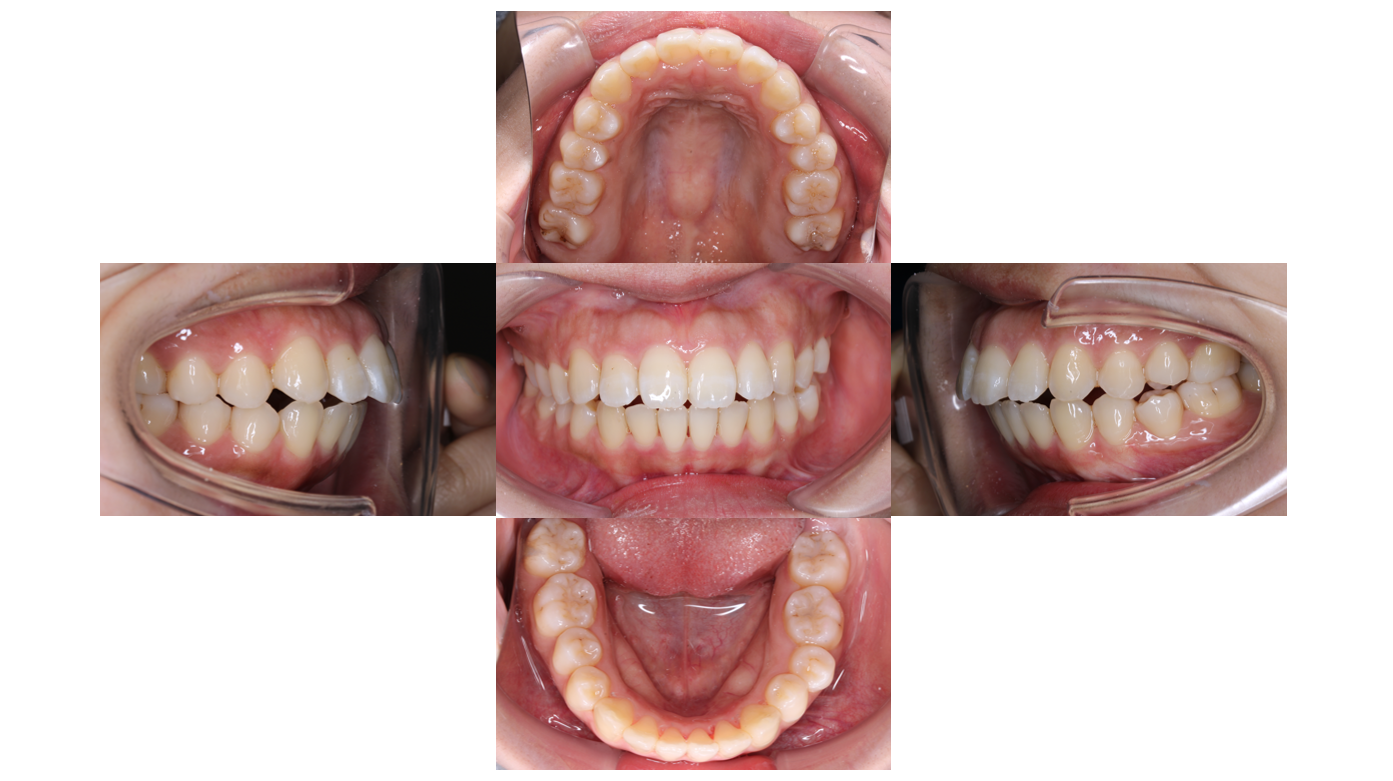

After

2年経過

全体的にゴムをかけて隙間が空いてこないようにします